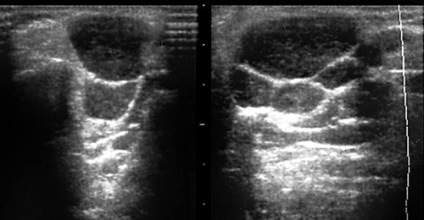

A rengeteg limfoid szövet a mirigyeket okoz nagy gyakorisággal a léziók jóindulatú vagy rosszindulatú limfoproliferatív rendellenességek, amelyek szintén megvan a saját jellemző echográfiás jelek (ábra. 38-39).

Ábra. 38. A vereség maradt fültőmirigy limfoproliferatív betegség (szövettanilag: limfóma).